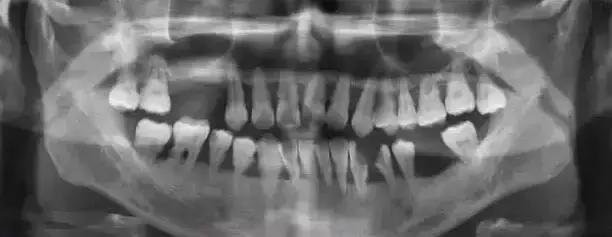

2.牙石 牙石是指沉积在牙面上的矿化的菌斑,根据其沉积部位和性质分为龈上牙石和龈下牙石两种。

(2).龈下牙石:位于龈缘以下、龈袋或牙周袋内的根面上,肉眼不能直视,必须用探针探查,方能知其沉积部位和沉积量。龈下牙石中无机盐的主要来源是龈沟液。 牙石对牙周策划的危害,主要是构成了菌斑附着和细菌滋生的良好环境。